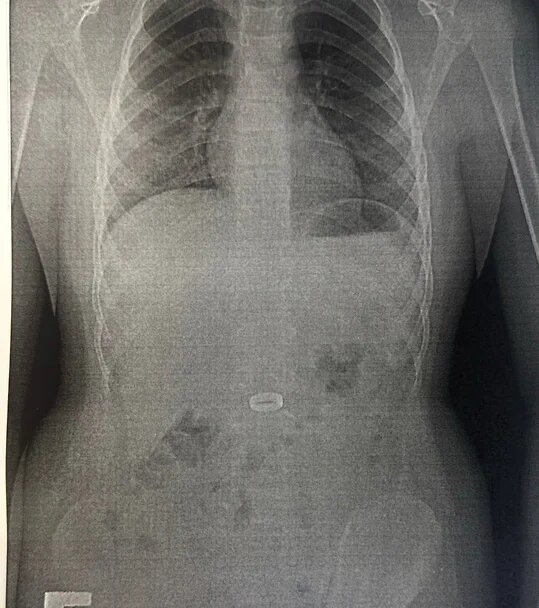

В Новороссийске врачи городской больницы №1 успешно провели операцию по извлечению кольца из желудка 11-летнего мальчика, который случайно проглотил ювелирное изделие. Пациент, страдающий от особенностей развития, был срочно доставлен в детское хирургическое отделение после того, как инородное тело не могло выйти из организма естественным путем. Согласно информации, опубликованной в официальном Telegram-канале медицинского учреждения, кольцо оказалось слишком крупным, чтобы пройти через желудочно-кишечный тракт, и оставаться внутри могло привести к серьезным повреждениям, таким как эрозия или язвы на стенках желудка. Попытки извлечь кольцо с помощью обычных щипцов не увенчались успехом: кольцо соскальзывало из-за своей ширины. Врачи решили воспользоваться специализированным инструментом — так называемой «корзинкой» для извлечения инородных тел, которая позволяет аккуратно захватить предмет и безопасно провести его через узкие части желудочно-кишечного тракта. Как рассказал заведующий о

Как рассказал заведующий отделением Давид Шагинян, случай оказался довольно сложным с технической точки зрения. Круглая форма и гладкая поверхность кольца значительно затрудняли процесс захвата. "Потребовалась точность и терпение, чтобы не повредить ткани", — отметил врач, добавив, что операция прошла успешно, и в настоящее время состояние ребенка стабилизировалось. Он чувствует себя хорошо и уже вскоре сможет вернуться к нормальной жизни.